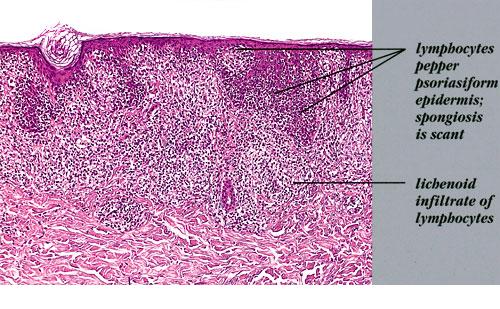

Mycosis Fongoïde =التفطر الكمئي